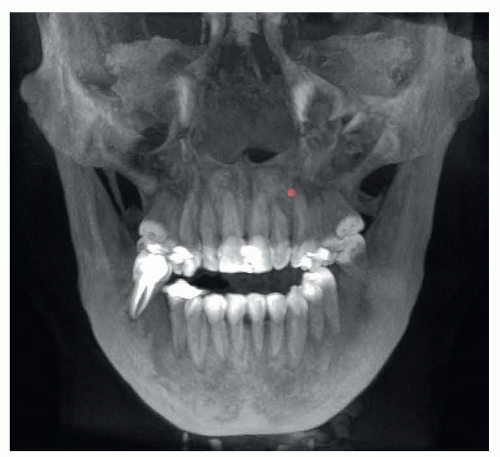

FIG 1 • Cone-beam computer tomography showing maxillary transverse deficiency.

• Cone-beam computer tomography (CBCT; FIG 1)